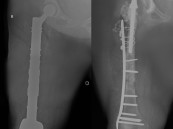

مستشفى الحبيب بالخبر يستبدل مفصلي الركبة والورك وعظمة الفخذ ويعيد “الحركة” لـ”ستينية”

تمكن مستشفى الدكتور سليمان الحبيب بالخبر، من إعادة القدرة على الحركة والمشي لسيدة ستينية، ظلت طريحة الفراش منذ أكثر من "14" عاماً، بسبب مضاعفات عملية استبدال مفصل الورك الأيمن كانت قد خضعت لها قبل "30" عاماً، وأجرى لها فريق طبي ...